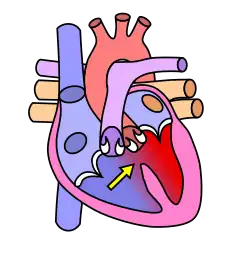

Cœur normal.

Communication interventriculaire haute.

Dans le cœur normal, la cloison qui sépare les ventricules droit et gauche, dénommée « septum interventriculaire », est totalement hermétique. Une CIV correspond à la présence d'un orifice plus ou moins large dans cette cloison, permettant le passage direct du sang d'un ventricule à l'autre. Les conséquences de cette malformation dépendent essentiellement de la taille de la communication. Dans la plupart des cas, l'orifice est petit : ces CIV sans conséquence réellement gênante sont appelées « maladie de Roger ». L'évolution d'une CIV dépend de sa localisation sur le septum, certaines étant susceptibles de se fermer spontanément dans les mois ou années suivant la naissance.